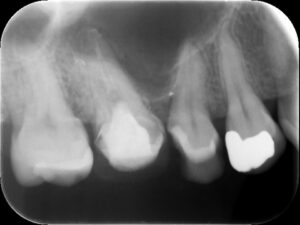

右側上顎第一大臼歯の初診時レントゲン。他院にて根管治療を行っているが良くならず、歯がひびく、黄色い鼻水が続いているとのこと。耳鼻科にて歯性上顎洞炎の診断を受ける。